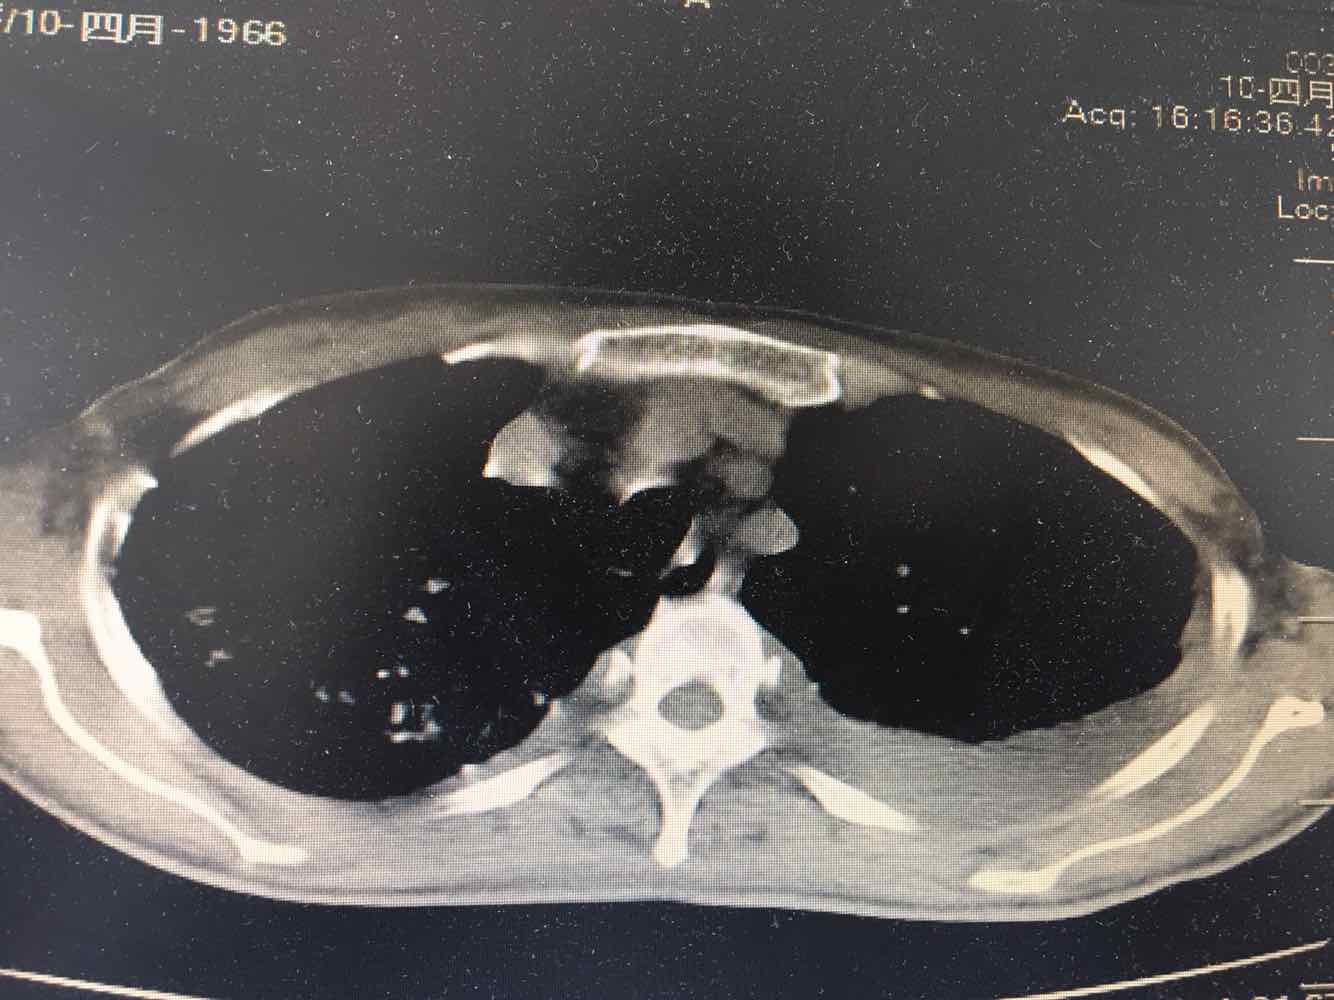

女,51岁,支气管扩张病史多年。慢性咳嗽咳痰喘息30年,加重1个月,无发热,气短为主,痰液不多,上腹不适,少尿。双肺干湿罗音。